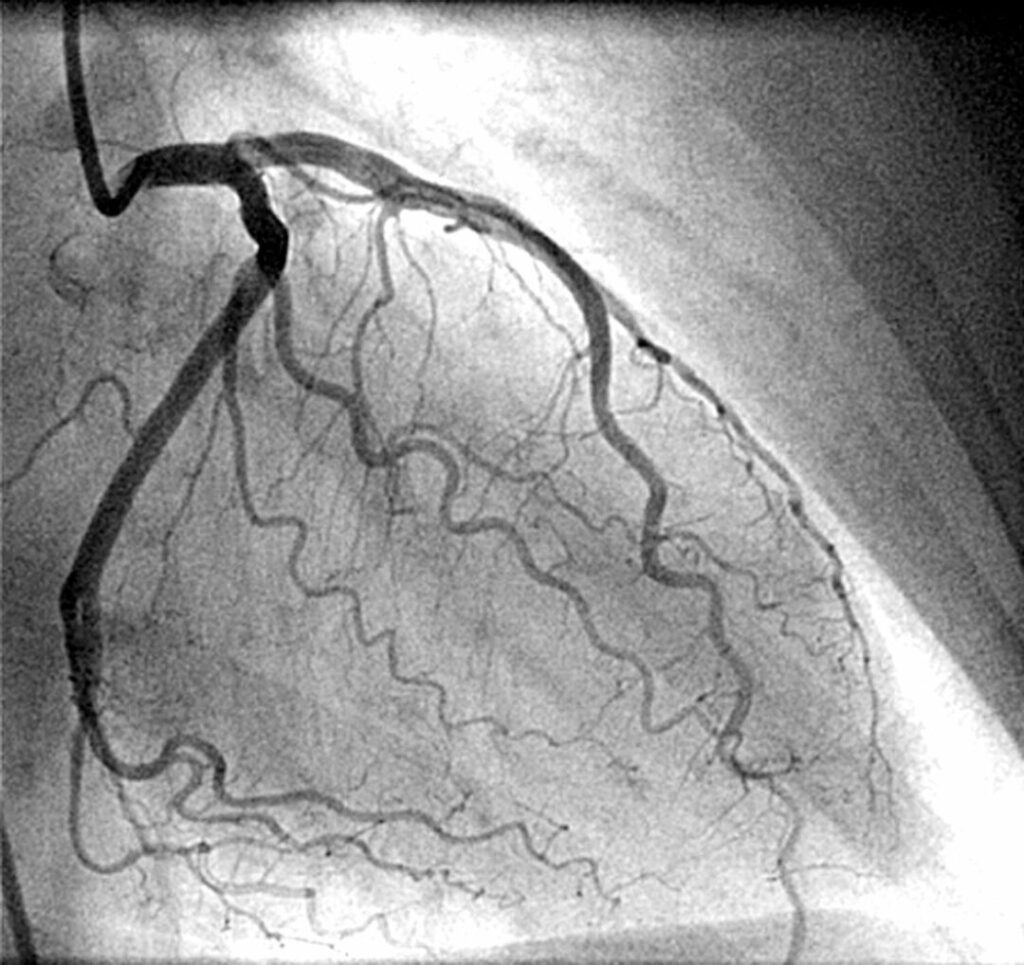

Это исследование позволяет врачу в режиме реального времени увидеть подробную “карту” ваших коронарных артерий. С помощью специального рентгеновского аппарата (ангиографа) и контрастного вещества мы получаем четкое изображение каждого сосуда, каждой веточки. Врач может с миллиметровой точностью определить:

3. Введение контраста и “съемка”. Когда катетер достигает цели, через него порциями вводится рентгеноконтрастное вещество на основе йода. В этот момент вы можете почувствовать волну тепла, расходящуюся по всему телу. Это нормальная и быстро проходящая реакция. В момент введения контраста ангиограф делает серию снимков (ангиограмм) под разными углами. Врач может попросить вас задержать дыхание на несколько секунд для получения более четкого изображения.